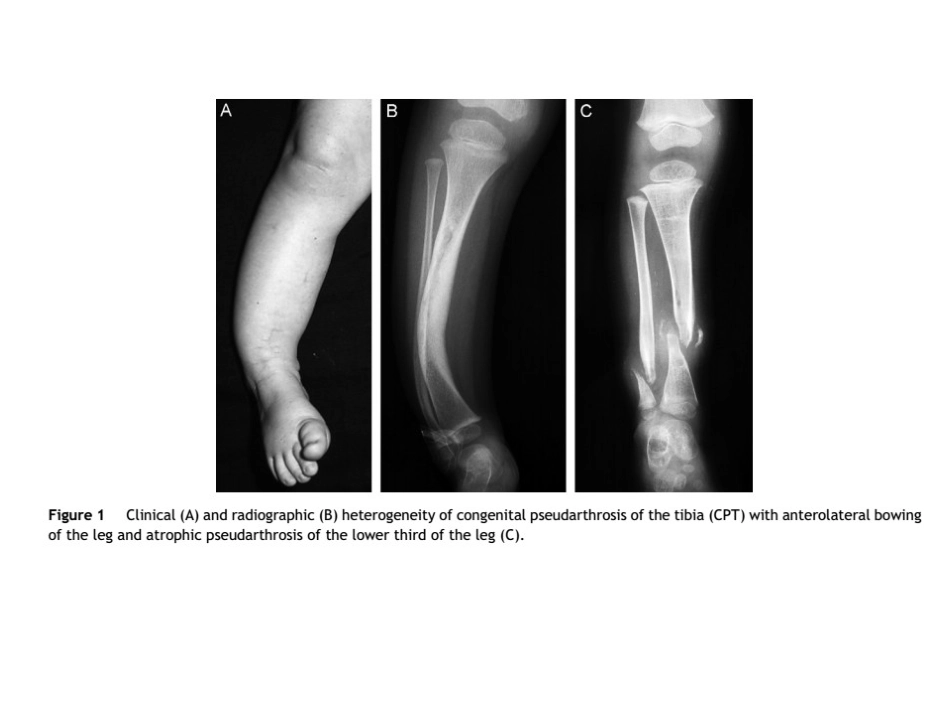

先天性胫骨假关节概念•先天性胫骨假关节(congenitalpseudarthrosisofofthetibia,CPT)是发生在儿童的一种罕见疾病•是一种特殊的骨不连,与神经纤维瘤病有一定关系•是由于天生或发育异常导致的胫骨畸形,表现为胫骨成角畸形、髓腔狭窄或者囊肿等,最终形成不愈合的假关节。•在所有儿童先天性疾病中先天性胫骨假关节可能是最难治疗的之一,没有标准的治疗方式分型•较多,临床指导性较差•多采用boyd分型分型•Ⅰ型:出生时就出现胫骨缺如或胫骨向前弯曲。可有其他先天性畸形。分型•Ⅱ型:此型最为多见,常伴有神经纤维瘤病,预后最坏。•出生时胫骨有前弯的同时有假关节或伴有葫芦状(沙漏)狭窄。•在2岁前可有自发性骨折或轻伤引起骨折,统称为高危胫骨。•骨呈锥状、圆形和硬化状,髓腔闭塞。•在生长期,骨折复发很常见,随着年龄增长,骨折次数将减少,至骨骺成熟,骨折也不再发生。分型•Ⅲ型:较Ⅱ型为少,通常在胫骨中1/3和下1/3交界处发生天性囊肿。•胫骨向前弯曲可先或者后于骨折。•治疗后再发生骨折的机会小。分型•Ⅳ型:在胫骨中1/3和下1/3交界处有硬化段,并发生假关节。•髓腔部分或完全闭塞。•在胫骨皮质可发生不全骨折或应力骨折,逐渐扩展到硬化骨,待折断后,不会再愈合,骨折处增宽而形成假关节。•这类骨折预后较好,在骨折成熟不足之前治疗,效果较好。分型•Ⅴ型:在腓骨发育不良时,胫骨产生假关节,两骨的假关节可同时发生。•若病损限于腓骨,预后较好。•若病损发展至形成胫骨假关节,则其发展过程类似Ⅱ型。分型•Ⅵ型:这极少见。•因骨内神经纤维瘤或Schwann'scell瘤而引起假关节。•预后取决于骨内病损的侵袭性和治疗。治疗•取决于患儿年龄及是否再次骨折•开始行走后腿部应该使用蚌壳样支具加以固定和保护直至骨骼成熟•发展为假关节后,必须手术治疗•髓内固定及重建力线是手术的两个基本原则•假关节切除,骨短缩,补充植骨对手术成功有帮助•最坏的治疗结果是截肢,且比例不低手术方式•植骨-髓内棒-外固定架联合手术髓内棒联合植骨髓内棒联合Ilizarov环形外固定架包裹式自体髂骨植骨联合手术•Masquelet手术•Burnei手术•四合一骨融合术•MSC移植•药物与外科手术联合治疗BMP、BP、rhBMP和BP联合应用治疗•Intramedullarynailingassociatedwithabonegraft治疗•Intramedullarynailingassociatedwithabonegraft治疗•Vascularizedbonetransfers治疗•Ilizarovtechnique治疗•Ilizarovtechnique治疗•Inducedmembraneandspongyautologousgraft治疗•Osteoinduciveproteinsorbonemorphogeneticproteins治疗治疗并发症•踝关节及足的僵硬•骨折•踝外翻畸形•胫骨短缩